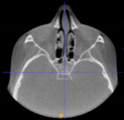

Three points determined the Acta plane: O, F right (FR), and F left (FL) (Table 2). Point O is the midpoint between the most craniodorsal point of the dorsum Sella and the most posterior dorsal point of the Basion in the midsagittal plane (Figure 1). Both points F are a result of the intersection between two lines: the line that connects the most inferior points of the lower orbital margins, right and left, and a line perpendicular to this line that runs through the most external points of the orbital margins, right and left (Figure 2). The new transverse reference plane, the Acta plane (Figure 2), is created by connecting the O-point (Figure 1) with FR and FL (Figure 2).

Figure 2.

(A) Construction of the F-points (right and left), frontal view. The F-points are originated from the intersection between the line connecting points A (the most inferior point of the lower orbit) and the perpendicular line to it that passes through points B (most external/lateral point of the Orbita). (B) Transverse view of the ACTA plane.